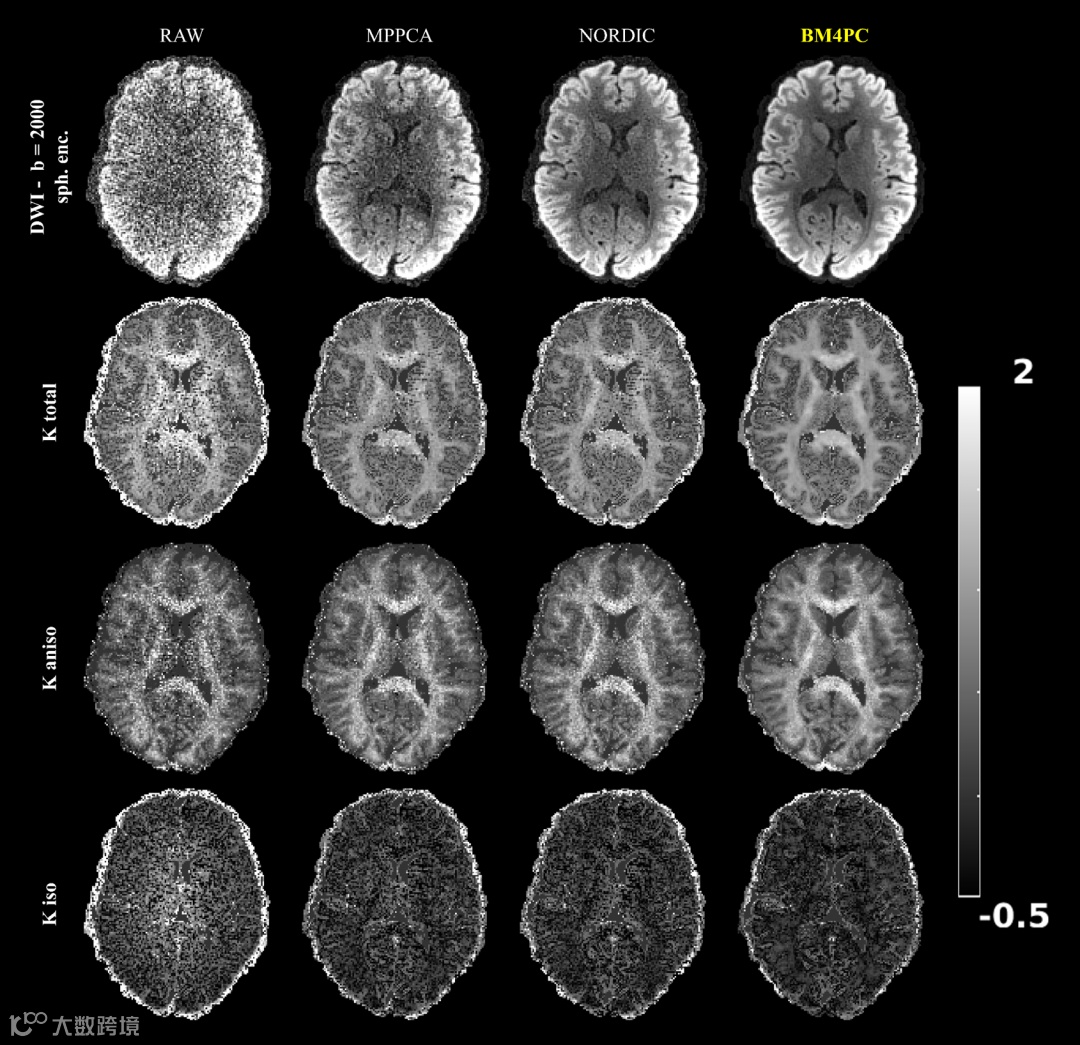

DWIs (with spherical tensor encoding) and Kurtosis metrics for Dataset 2.

BM4PC achieves the most striking result.

We reinforce that Kiso is highly sensitive to noise, with considerably large increases in the values when no denoising is used. Ktotal and Kaniso retain their exquisite white/grey matter contrast and high-resolution features for all denoising approaches, but BM4PC results in the lowest propagation of noise.